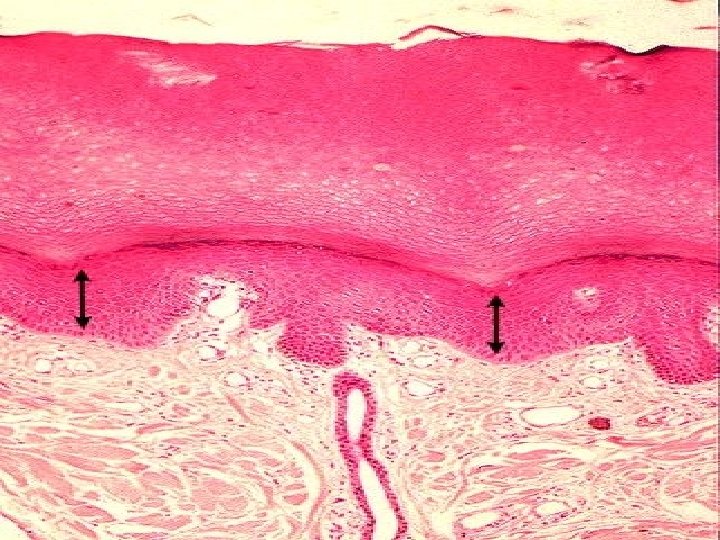

TYPES OF SKIN • Thin skin – covers all parts of the body except for the palms and palmar surfaces of the digits and toes. – lacks epidermal ridges – has a sparser distribution of sensory receptors than thick skin. • Thick skin (0. 6 to 4. 5 mm) – covers the palms, palmar surfaces of the digits, and soles – features a stratum lucidum and thick epidermal ridges – lacks hair follicles, arrector pili muscles, and sebaceous glands, and has more sweat glands than thin skin.

Specific Layer of the Epidermis Stratum Lucidum: • Observed only in nonhairy or thick skin. Several layers of dead cells with indistinct boundaries Stratum Corneum: • Composed of 25 or more layers of dead squamous cells still joined by desmosomes. Eventually desmosomes break and cells flake off in a process called desquamation